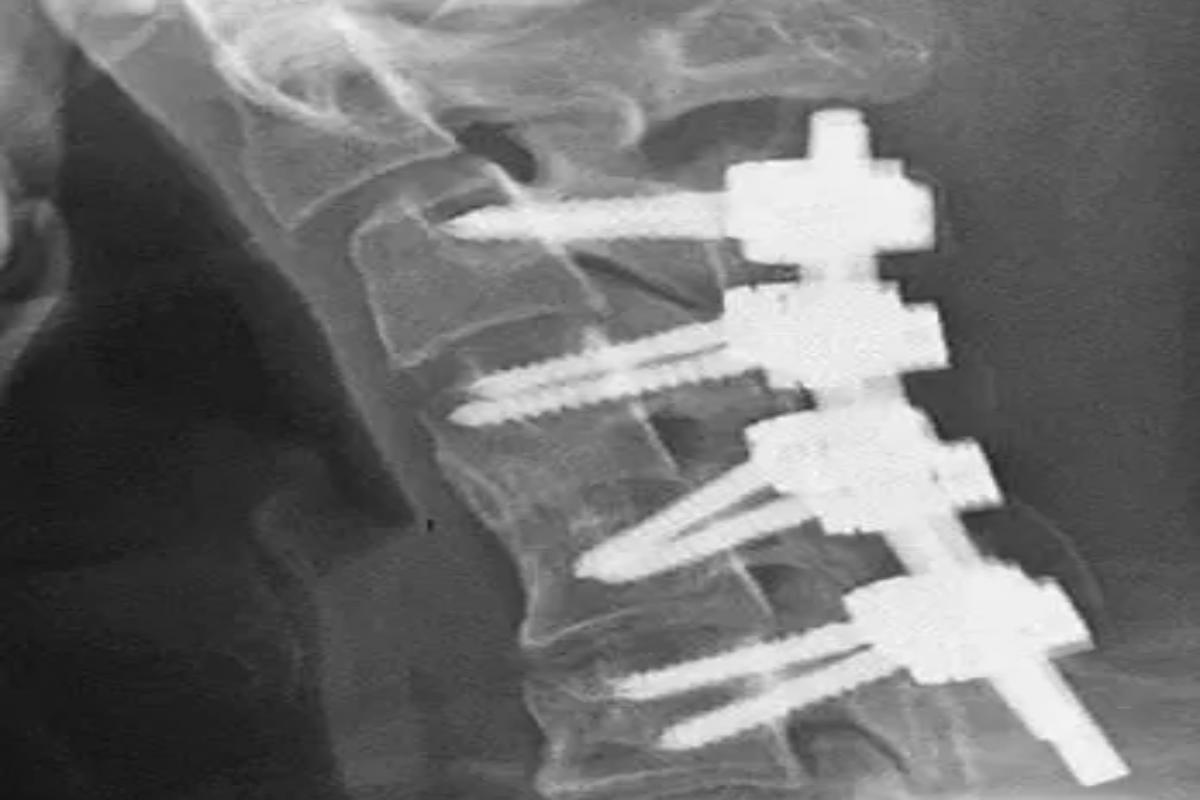

Il ragazzo ha iniziato così ad accusare fortissimi dolori al collo, oltre alla difficoltà di deglutire correttamente, una condizione che lo ha portato anche a perdere sensibilmente peso. Nel tempo, il suo collo era diventato così debole che il ragazzo non riusciva più a sollevare la testa. Dopo un primo consulto medico, si è cercato di alleviare il suo dolore attraverso l’utilizzo di un collare ortopedico. La cura, rivelatasi inutile, è stata sospesa dopo poche settimane, a causa del dolore che il ragazzo continuava a lamentare. Alla fine, si è deciso di percorrere la via dell’operazione chirurgica, sviluppatasi in più fasi. I medici hanno prima rimosso piccoli segmenti delle vertebre compromesse e parte del tessuto cicatriziale. Poi hanno impiantato una struttura di viti e barre metalliche nelle ossa cervicali per correggere la postura del ragazzo.

Alla fine, il complicato intervento ha dato i suoi frutti e diversi mesi dopo l’operazione il paziente era di nuovo in grado di mantenere la testa sollevata attraverso una postura corretta. Con la pubblicazione di questo studio dettagliato, i medici hanno cercato di sottolineare quali possono essere le possibili e gravi conseguenze di una postura scorretta prolungata quando si è eccessivamente chinati sullo schermo del telefono, rivelando quanto i casi relativi a questo fenomeno siano in costante aumento.